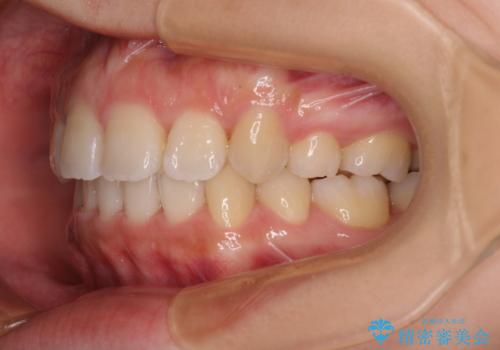

4本の歯を抜歯したことで、飛び出していた口元が引っ込み、横顔の印象が大きく改善されました。